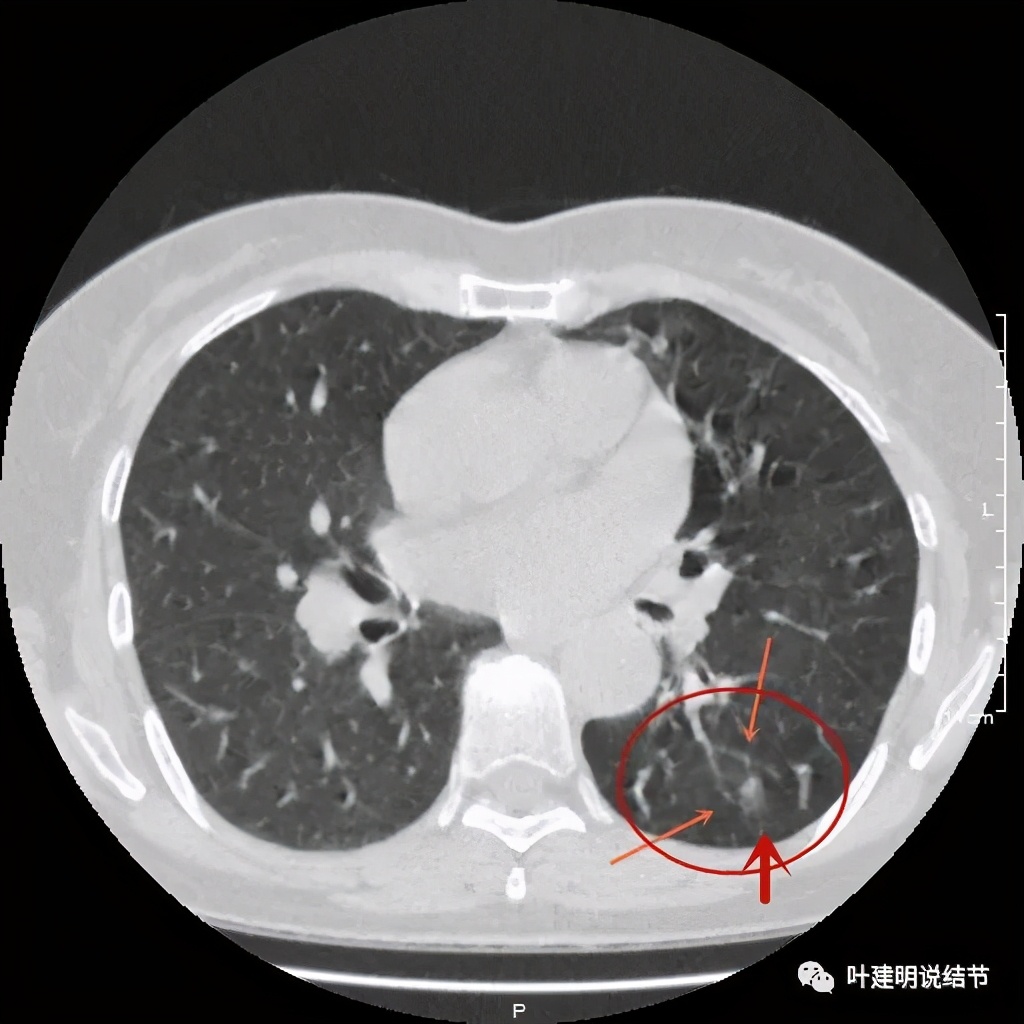

金华的某A,女性,56岁,去年8月份检查发现左肺下叶结节,是实性的,还中间有个空洞,我们说若磨玻璃结节伴空泡或空腔多为恶性范畴的,实性的也是可能性会大一些,但不如磨玻璃确切,因为结核、感染等也会类似的。我们先来看她当时的CT图像:

左下结节与血管关系密切,此层似磨玻璃结节,还夹在小血管之间,其中有血管紧贴病灶,略迂曲